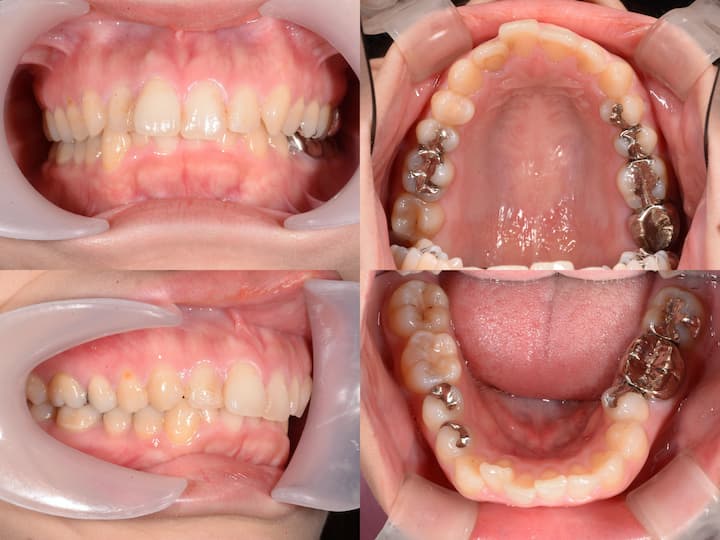

開咬(オープンバイト)のマウスピース矯正治療

Before

After

治療期間: 1年6ヶ月

前歯が噛み合っていないため、上顎臼歯を圧下(上方向に移動)し、上顎前歯は挺出(下方向に移動)して治療を行いました。

大臼歯の圧下と上顎前歯の挺出

上顎大臼歯の圧下(上方向に移動)と上顎前歯の挺出(縦に伸ばす)を行いました。下顎前歯は極力挺出させず、下顎骨の回転により前歯を噛み合わせるような治療計画を立てました。

開咬(オープンバイト)は後戻りにより、治療後に再び前歯が噛み合わなくなるリスクがあります。大臼歯の圧下のみや前歯の挺出のみの治療ではそれぞれの歯の移動量が大きくなり後戻りのリスクが大きくなります。 したがって大臼歯の圧下と前歯の挺出を組み合わせることでそれぞれの歯の動きをできるだけ小さくして後戻りのリスクを減らしています。このケースでは治療終了2年後に前歯が噛み合う状態を維持できています。